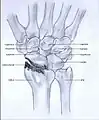

SNAC

Scaphoid nonunion advanced collapse

Scaphoid fracture non-union changes the shape of the scaphoid bone and results in DISI malalignment.[2][5] Scaphoid Non-union Advanced collapse (SNAC) is the pattern of osteoarthritis that develops in relation to the malalignment.

In order to diagnose a SNAC wrist you need a PA view X-ray and a lateral view X-ray. As in SLAC, the lateral view X-ray is performed to see if there is a DISI.[12] Computed tomography (CT) or Magnetic Resonance Imaging (MRI) are rarely used to diagnose SNAC or SLAC wrist osteoarthritis because there is no additional value.[7] Also, these techniques are much more expensive than a standard X-ray. CT or MRI may be used if there is a strong suspicion for another underlying pathology or disease.[7]